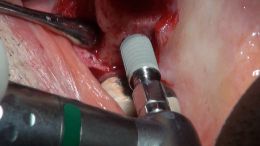

اصول مبانی GBR

+ اساتید گروه علمی بن تاژ پارس (زیرنظر پروفسور غلامی)

- جراحي توسط دکتر عميد از اساتید گروه علمی بن تاژ